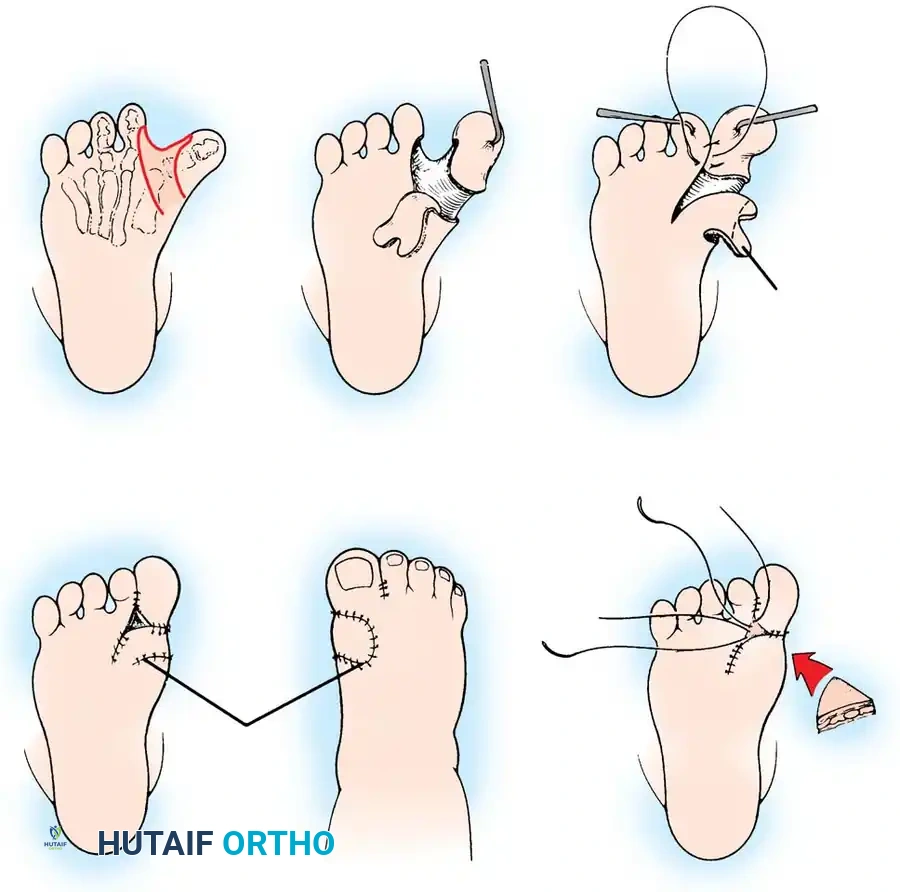

Step-by-Step Procedure

- Positioning and Preparation: The patient is placed supine on the operating table. A well-padded thigh tourniquet is applied. Fluoroscopy must be available.

- Surgical Approach: Approach all five metatarsal bases dorsally. Make two longitudinal dorsal incisions:

- Medial Incision: Placed between the first and second metatarsals.

- Lateral Incision: Placed overlying the fourth metatarsal.

- Dissection: Carefully dissect through the subcutaneous tissues. Meticulously protect the extensor tendons and branches of the superficial peroneal nerve. Preserve the superficial dorsal venous network as much as possible to prevent postoperative edema.

- Exposure: Subperiosteally expose the proximal metaphysis of each of the five metatarsals.

- Osteotomy: Using a small power drill or a specialized crescentic oscillating saw blade, create a dome-shaped osteotomy in each metatarsal base.

- Crucial Detail: The apex of the dome must point proximally.

- Pitfall Avoidance: Strictly avoid the physis at the base of the first metatarsal, which is located proximally.

- Correction and Wedge Resection: Manipulate the forefoot into abduction. If adequate correction cannot be obtained solely by rotating the dome osteotomies (due to severe lateral column shortening), resect small wedges of bone based laterally at the osteotomy sites as needed.

- Fixation: Align the metatarsals and transfix the foot in the corrected, plantigrade position. Insert small, smooth Steinmann pins (or heavy Kirschner wires) proximally through the shafts of the first and fifth metatarsals, crossing the osteotomy sites into the respective cuneiforms and cuboid.

- Ensure there is no dorsal or volar angulation, and prevent overriding of the osteotomy fragments.

- Radiographic Confirmation: Before closure, utilize fluoroscopy to check pin placement, osteotomy apposition, and overall forefoot alignment. The anteroposterior talus–first metatarsal angle should be corrected to 0 to 10 degrees.

- Positioning: The anesthetized patient is placed supine. A thigh tourniquet is utilized.

- Lateral Approach (Cuboid): Make a small longitudinal incision directly over the cuboid.

- Cuboid Osteotomy: Perform a closing wedge osteotomy of the cuboid. Remove a 7- to 10-mm wedge of bone with its base oriented dorsolaterally. Preserve this bone wedge carefully, as it will be used as the graft for the medial side.

- Medial Approach (Cuneiform): Approach the medial cuneiform either by extending a medial incision or by making a dedicated 2-cm longitudinal incision medially over the medial cuneiform.

- Cuneiform Osteotomy: Perform a transverse osteotomy through the mid-substance of the medial cuneiform.

- Surgical Pearl: Leave the insertion of the anterior tibial tendon attached to the distal fragment of the medial cuneiform to maintain dynamic control of the medial column.

- Graft Insertion: Insert a vertebral lamina spreader into the medial cuneiform osteotomy and gently distract it. Take the bone wedge previously harvested from the cuboid and insert it into the medial cuneiform defect. The base of the wedge should face straight medially.

- Assessment of Correction: Evaluate the clinical correction. If the lateral border of the foot remains prominent (indicating uncorrected midfoot supination or adduction), return to the lateral side and resect a larger wedge of bone from the cuboid.

- Fixation: Fix the foot in the corrected position using two smooth Kirschner wires:

- Lateral Pin: Start in the calcaneus, pass through the cuboid osteotomy, and exit through the base of the fifth metatarsal.

- Medial Pin: Insert through the first web space, pass down the shaft of the first metatarsal, through the grafted medial cuneiform, through the navicular, and anchor into the talus.

- Radiographic Confirmation: Confirm pin placement and bony alignment via fluoroscopy.

- Adjunctive Procedures: After correcting the midfoot, the lateral three toes may occasionally remain in passively uncorrectable flexion due to relative lengthening of the flexor tendons. If this occurs, perform simple percutaneous flexor tenotomies.

- Closure: Close the wounds in layers. Apply a short leg cast with thick cotton padding to accommodate anticipated postoperative swelling.